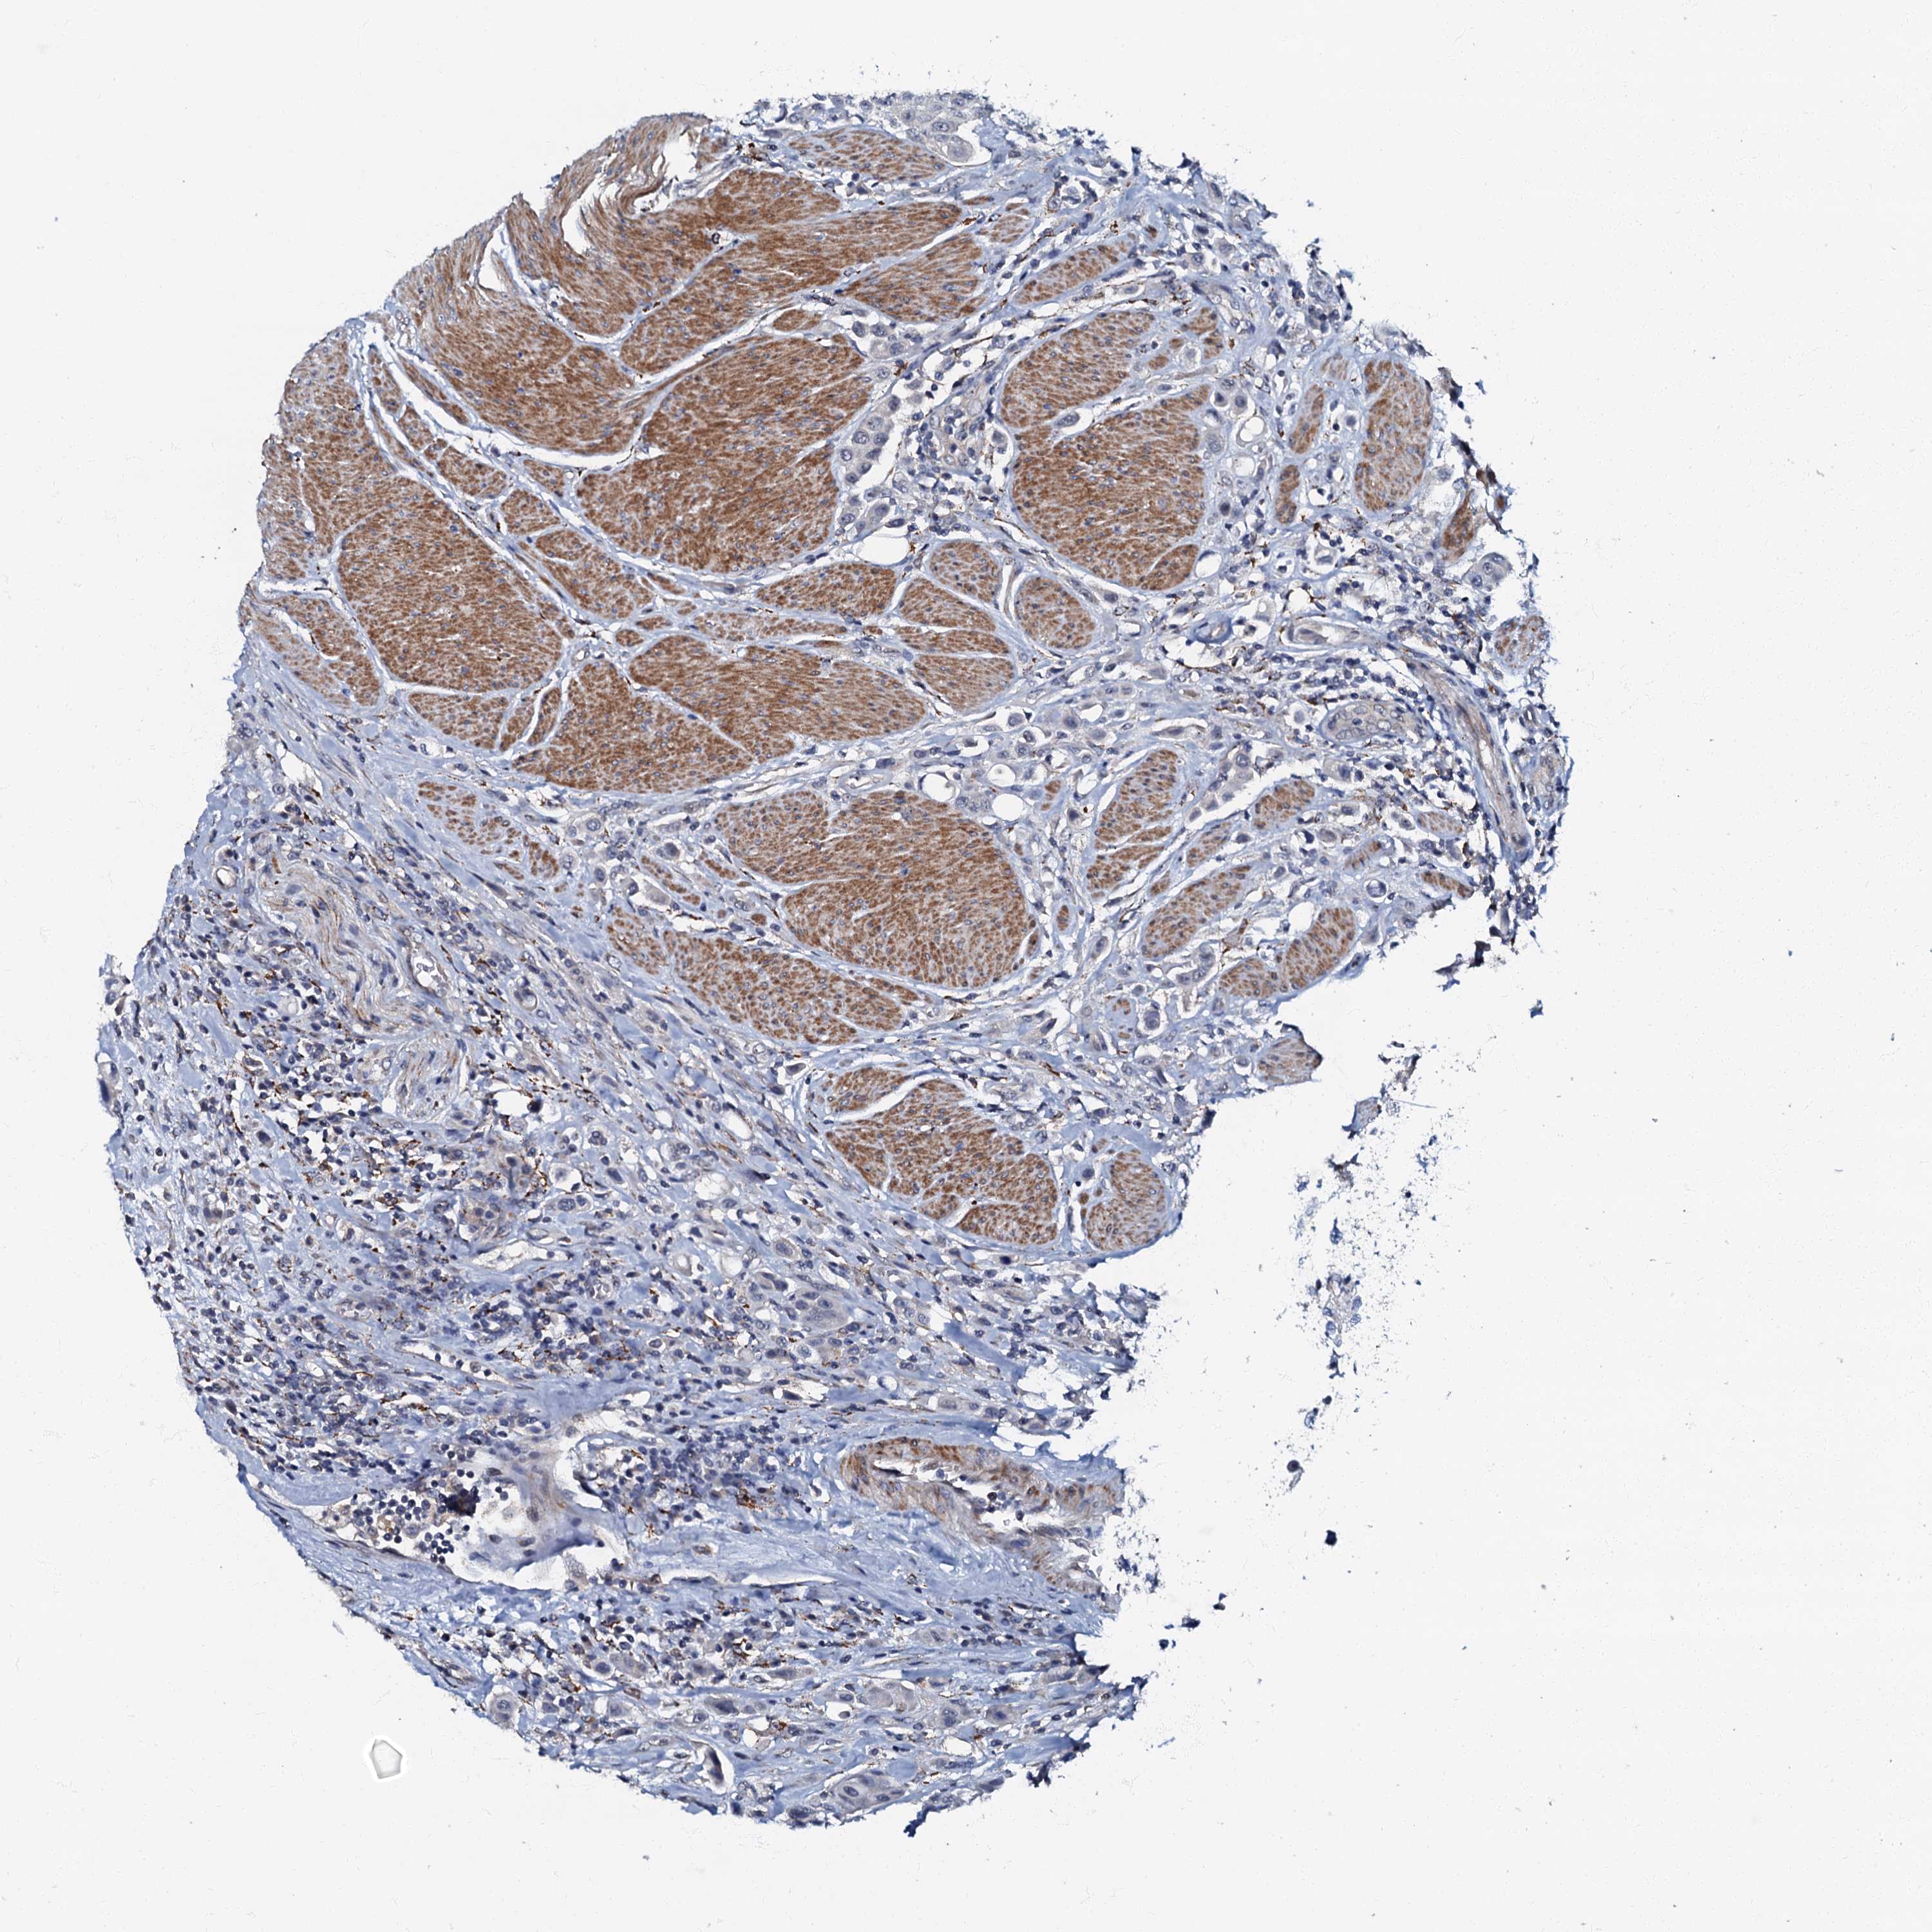

UROTHELIAL CANCER - Protein expressioni

A mouse-over function shows sample information and annotation data. Click on an image to view it in a full screen mode. Samples can be filtered based on level of antibody staining by selecting one or several of the following categories: high, medium, low and not detected. The assay and annotation is described here.

Antibody stainingi

Antibody staining in the annotated cell types in the current human tissue is reported as not detected, low, medium, or high, based on conventional immunohistochemistry profiling in selected tissues. This score is based on the combination of the staining intensity and fraction of stained cells.

Each image is clickable and will lead to virtual microscopy that enables deeper exploration of all samples and also displays staining intensity scores, fraction scores and subcellular localization as well as patient and tissue information for each sample.

Antibody HPA037947

Antibody HPA037948

Staining

High

Medium

Low

Not detected

Intensity

Strong

Moderate

Weak

Negative

Quantity

>75%

75%-25%

<25%

None

Location

Nuclear

Cytoplasmic/membranous

Cytoplasmic/membranous,nuclear

Urothelial carcinoma, High grade

Urothelial carcinoma, Low grade

Urothelial carcinoma, NOS